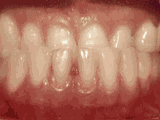

症状表现:上牙边沿覆盖下牙超过1/3,俗话说的天包地。

症状表现:疾病外因等造成的牙列稀疏,牙槽骨过长或牙齿缺失,导致排列太宽松,零零散散。

症状表现:下牙边沿覆盖上牙超过1/3,俗话说的地包天。